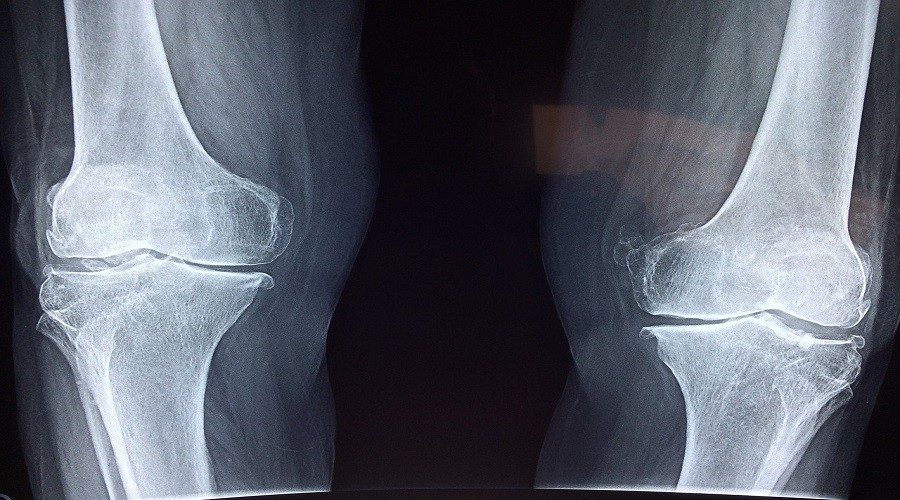

"Bu sebeple diz kıkırdaklarına ve özellikle diz kapağı kıkırdaklarına aşırı yük binmektedir. Merdiven inip çıkma, çömelme gibi hareketler esnasında bu yük kişinin ağırlığına göre birkaç yüz kiloya kadar çıkabilir. Vücudun en kalın kıkırdak tabakası diz kapağının arka kısmındadır. Dizde kıkırdak bozulması ve kireçlenme belli bir yaş sonrası kendiliğinden başlayabileceği gibi, travma, menisküs yaralanmaları veya romatizmal hastalıklar dizde kireçlenmeye sebep olabilir. Ekrem kireçlenmesi genellikle ağrıyla başlayıp, sonrasında hareket kısıtlılığı, fonksiyon kaybı ve kıkırdak kaybına neden olmaktadır. Bir süre sonra da dizde şişlik şekil bozukluğu ortaya çıkar" diye konuştu.

"Kişinin diz kapağının arkasını döşeyen kıkırdağın yıpranmasının ve aşınmış olmasının ilk belirtisi dizden ses gelmesidir. Çıtırdama şeklinde meydana gelen bu sesler çömelirken, çömelip kalkarken ortaya çıkmaktadır. Bu sesin en büyük sebebi diz kapağı kıkırdağının yüzeyinin bozulması ve hareket halinde bu bozuk yüzeyin karşı kemik yüzeye sürtmesindendir. Bu duruma da "Kondromalazi Patella" denir. Ancak bazen dizden gelen kütleme şeklinde duyulan ses de meniskus yırtığı nedeniyle de oluşabilir.

Dizden ses gelmesi genellikle ileri ve orta yaş gruplarında meydana gelir. Ama genç kişilerde de oluşabilir. 35-40 yaşlarında dizlerden ses geliyorsa bu erken kireçlenmenin belirtisi olabilir.Sesle birlikte ağrı meydana geliyorsa ve bu ağrı özellikle oturup kalkmada, diz kırarak yapılan hareketlerden sonra duyuluyorsa mutlaka bir Fizik Tedavi Uzmanına başvurulmalıdır. Ağrı olmasa bile dizden ses gelmesi inceleme gerektirir. Seçilecek en doğru yöntem kıkırdak dokuyu ayrıca menisküsleri çok iyi görebilmesi nedeniyle (MR) çekilmesidir. MR ile diz kemiklerinin kıkırdakları ayrıntılı bir şekilde gösterilebilmektedir.''